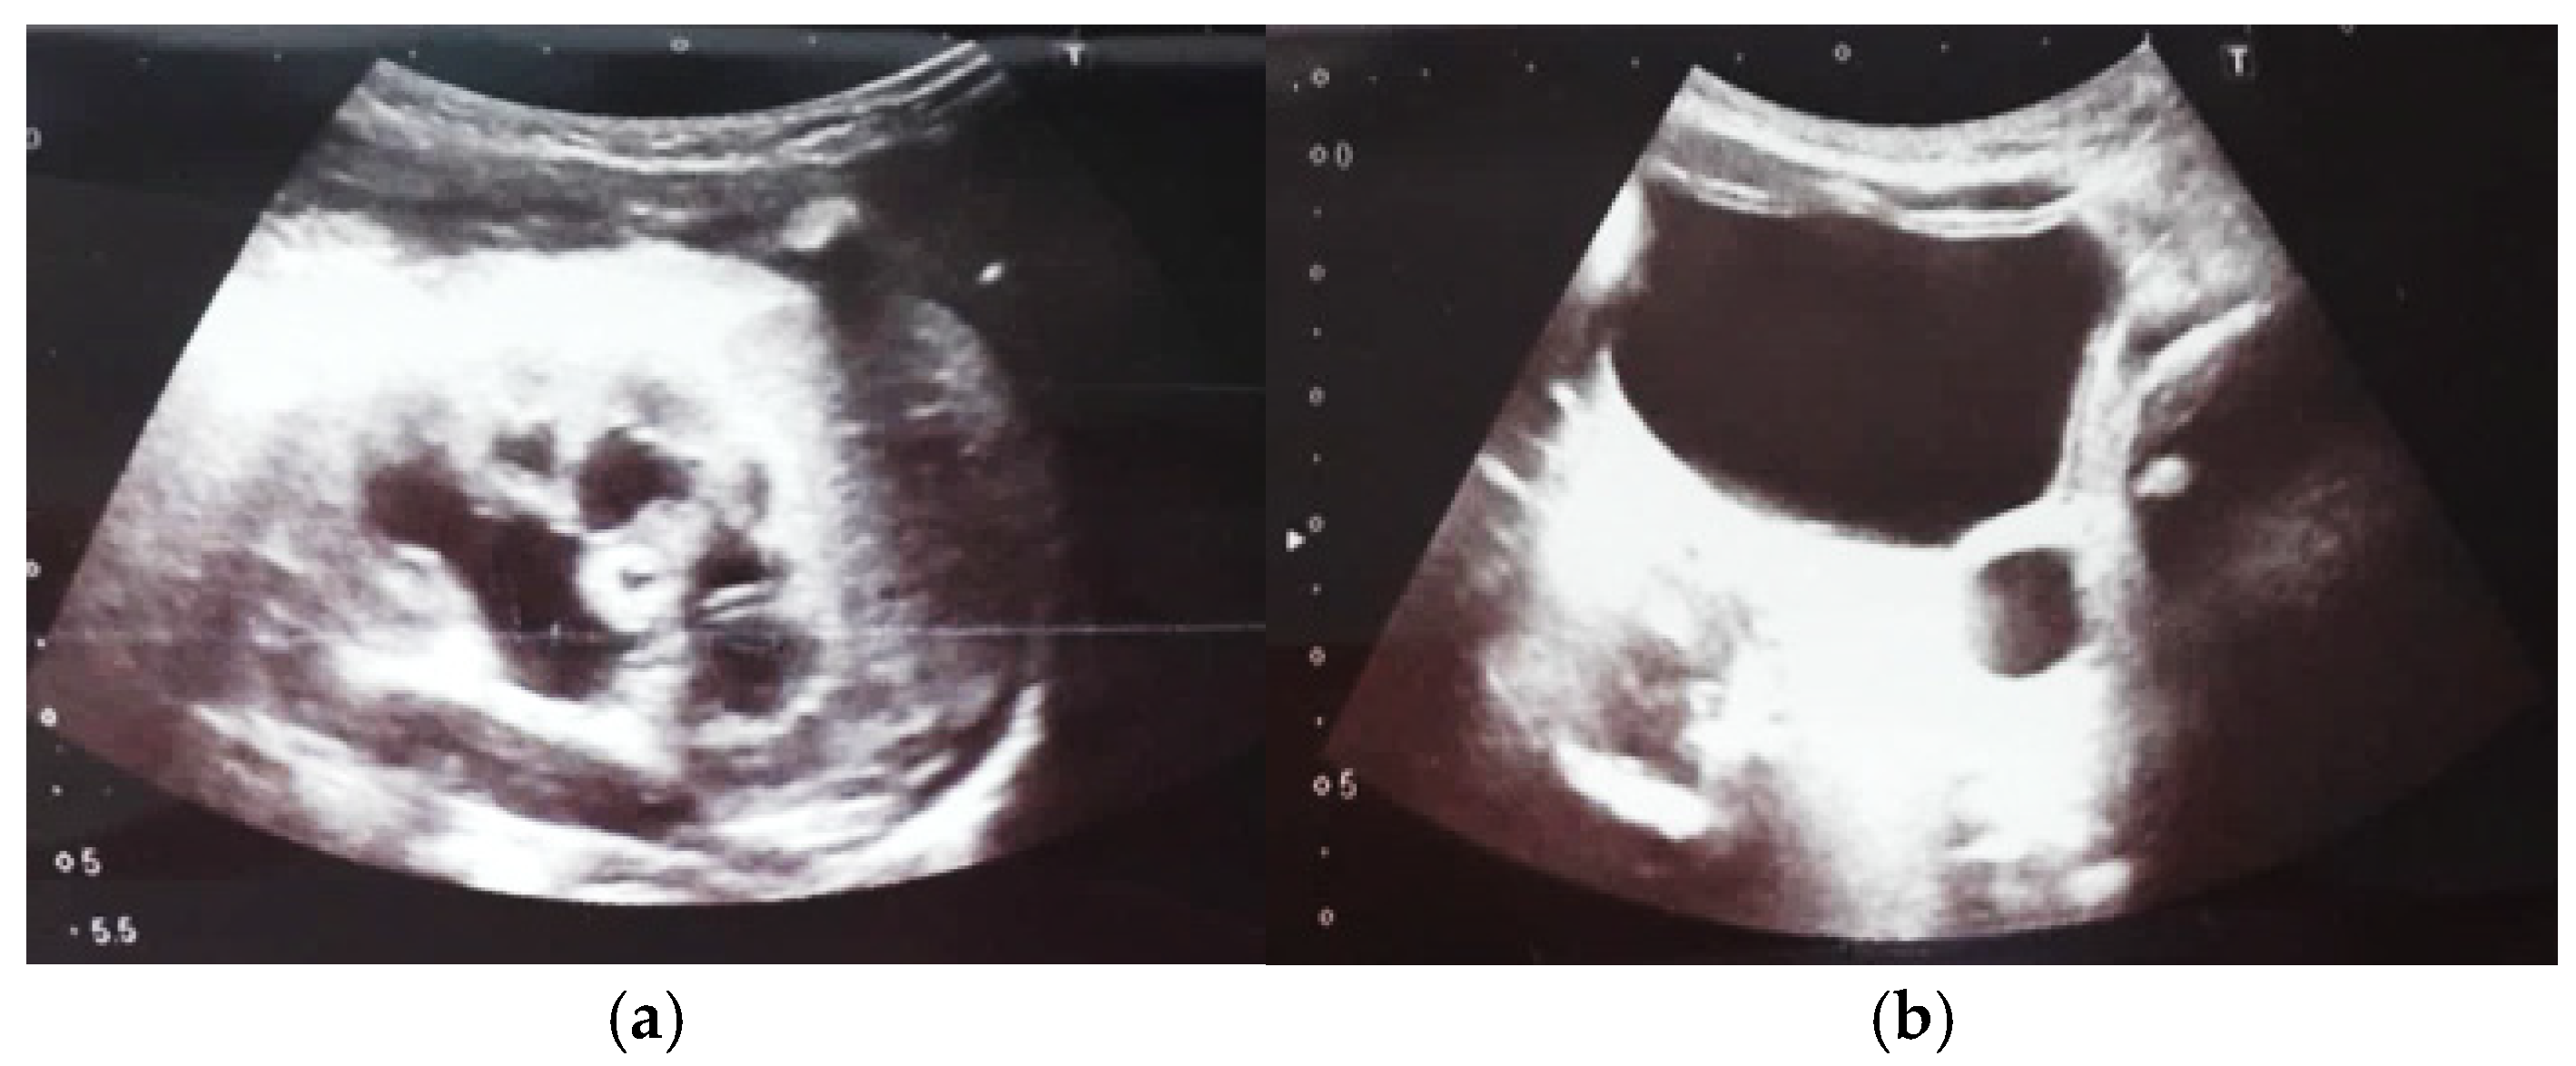

Figure 9. Ultrasound of the urinary system in a 12-day-old newborn. Hydrocalconephrosis on the left (a) and ureteral hydronephrosis on the right (b).

Our experience with congenital malformations of the urinary system refers to the following clinical case (Figure 2, Figure 3, Figure 4, Figure 5, Figure 6, Figure 7, Figure 8 and Figure 9). In the first case, during pregnancy, the 21-week ultrasound determined bilateral renal pyelectasia. The fetus had hydronephrosis on the right; at 31 weeks, it had bilateral hydrocalconephrosis; and at 32 weeks, bilateral pyelectasia. It suffered premature birth at 36 weeks, with complicated anomalies of the forces of contraction, prolonged birth, and birth weight of 2200 g. Postnatal ultrasonography was supplemented by intravenous urography, and bilateral hydronephrosis was determined. Hydrocalconephrosis on the left was discovered. The complete diagnosis was established: congenital renal malformation; bilateral pyelectasia; bilateral hydronephrosis; hydrocalconephrosis on the left; and severe reduced glomerular filtration rate (GFR), GFR > 2SD below mean.